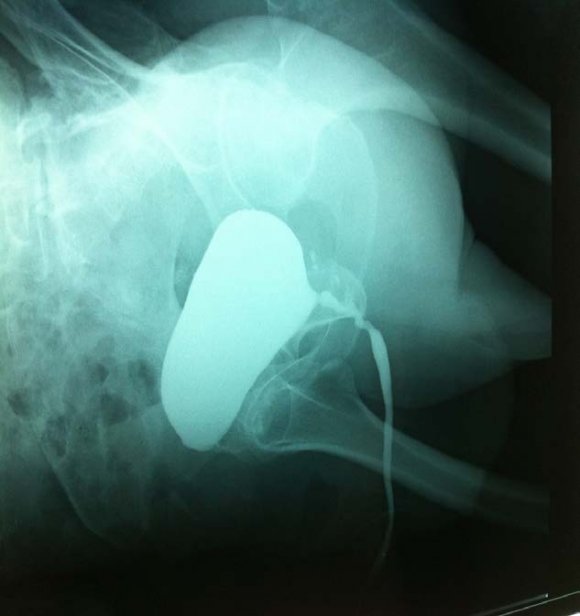

A 45-year-old man presented with mild to moderate lower urinary tract symptoms (LUTS) of one year duration with frequent history of catheterizations for urine retentions. He has no past history of infection, urethral stricture disease, or benign prostatic hypertrophy. The patient was comfortable and had no sensation of needing to void. The physical examination reveals no sensitive or motor deficits. A catheter was placed but the patient was unable to void after the catheter was removed. A postvoid residual volume obtained by noninvasive bladder ultrasonography reveals 1000 mL (figure 1). Retrograde and voiding urethro-cystography was normal (figure 2). The uroflowmetry result of the patient was Qmax: 6, 3 mL/sec. Cystoscopy reveals no obstructive lesions and a normal-appearing urethra, prostatic fossa, and bladder. Urodynamic testing demonstrated a normal capacity, compliant bladder The patient was unable to sense filling at any volume and is also unable to generate any voiding contraction (figure 3). Examination of the peripheral blood showed the red blood cell count to be 2, 2 million, WBC 28oo, hemoglobin 7.9 Gm. per 300 cc., hematocrit 28 per cent, and average cell volume 12.7 Cu. microns. In the stained blood films the erythrocytes varied greatly in size and in shape, reticulocytes were slightly less than a per cent, and the percentage of neutrophils was reduced with many of them having multilobed nuclei. Laboratory exams showed also revealed Serum antibodies to gastric parietal cells in the peripheral blood examination, the diagnosis of pernicious anemia was selected by highlighting a chronic gastritis fundic atrophy and intrinsic factor antibodies. The patient was treated by vitamin B12 orally at 500 mg / day and received a folic acid. The evolution was marked by a disappearance under treatment of urinary disturbances, macrocytosis correction and normalization of vitamin B12. At 6 months follow-up, clinical symptoms had improved, and postvoid residual (PVR) was 75 mL.